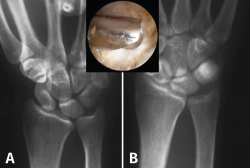

Típicamente, la osteotomía suele ser transversal u oblicua, y la osteosíntesis se lleva a cabo con una placa de compresión (Figura 4). Se realiza una incisión a lo largo del borde subcutáneo del cúbito. La longitud de la incisión está determinada por la longitud de la placa. La disección se lleva a cabo entre el ECU y el flexor carpi ulnaris (FCU). El periostio se incide longitudinalmente y se separa circunferencialmente. La placa debe proporcionar estabilidad y compresión con 3 tornillos bicorticales proximales y distales a la osteotomía. Algunas placas también permiten colocar un tornillo a compresión a través de la osteotomía cuando es oblicua.

Figura 4. A: muñeca con varianza cubital positiva; B: varianza corregida tras osteotomía de acortamiento cubital.

En nuestro servicio, además, consideramos recomendable y realizamos siempre una artroscopia diagnóstica de muñeca antes de la osteotomía. Inspeccionamos con ella las articulaciones cubitocarpiana, radiocarpiana, mediocarpiana e incluso la ARCD, y tratamos los hallazgos patológicos asociados que encontramos durante la exploración, como las lesiones del CFCT o lesiones osteocondrales de la articulación cubitocarpiana y el semilunar.

Existen dos condicionantes importantes para poder indicar la OAC: que la configuración coronal de la ARCD no sea reversa y que esta articulación no presente signos artrósicos. Si estos condicionantes no se tienen en cuenta, se producirá un aumento de la presión sobre la ARCD y se agravará la degeneración artrósica de la misma (transformando un SIC en un síndrome de impactación radiocubital distal).